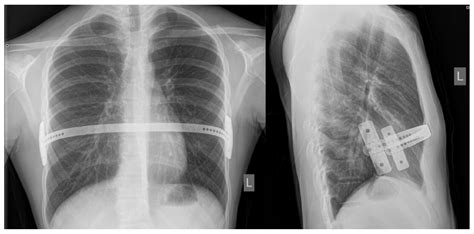

• Bar Insertion: A curved metal bar is inserted behind the sternum through the incision.

• Bar Flipping: The bar is then flipped, so the convex side faces the sternum, gradually pushing it outward.

• Closure: The incision is closed with sutures, and the bar is secured in place.

• Follow-Up Visits: Regular follow-up visits with the surgeon are essential to monitor the progress of the correction and ensure the bar is in the correct position.

• Bar Removal: The metal bar is typically left in place for 2 to 4 years, allowing the chest to grow and maintain its corrected shape. Once the chest has stabilized, the bar is removed in a separate outpatient procedure.